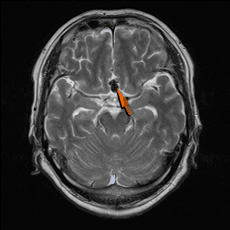

頭部MRI

• 頭部MRI正常

正常

• 頭部MRI無症候性脳梗塞

無症候性脳梗塞

• 頭部MRI脳動脈瘤

脳動脈瘤